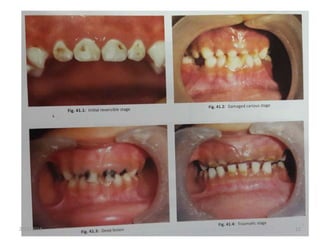

Developmental stages

Stage Clinical features Age Features

I Initial reversible stage 10-18months Cervically and occasionally interproximal

areas of chalky white demineralization.

No pain.

II Damaged carious stage 18-24months Lesion in maxillary anterior teeth,may

spread to dentin and show yellowish

brown discoloration.

Pain on having cold food.

III Deep lesion 24-36months Depending on time of

eruption,cariogenicity of sweetner and

frequency of its use this stage can reach

in 10-14months also.

Molars are also affected

Frequent complaint of pain

Pulpal involvement in maxillary incisors

IV Traumatic stage 36-48months Teeth becomes so weakened

Report of history of trauma

Molars associated with pulpal problems

Maxillary incisors become non vital.2/15/2016 10